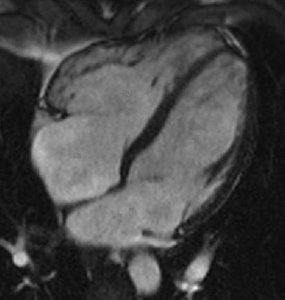

Restrictive cardiomyopathy is characterized by stiff ventricular walls that impede diastolic filling, while systolic function is often preserved until late stages.

Diagnosis: Echocardiography shows normal or increased wall thickness, normal ventricular dimensions, and dilated atria.